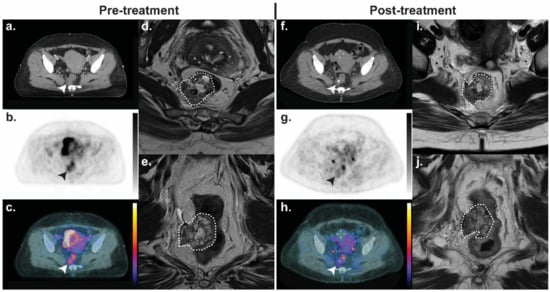

- Lewin, J.; Khamly, K.K.; Young, R.J.; Mitchell, C.; Hicks, R.J.; Toner, G.C.; Ngan, S.Y.; Chander, S.; Powell, G.J.; Herschtal, A.; et al. A phase Ib/II translational study of sunitinib with neoadjuvant radiotherapy in soft-tissue sarcoma. Br. J. Cancer 2014, 111, 2254–2261. [Google Scholar] [CrossRef] [PubMed]

- Horsman, M.R.; Mortensen, L.S.; Petersen, J.B.; Busk, M.; Overgaard, J. Imaging hypoxia to improve radiotherapy outcome. Nat. Rev. Clin. Oncol. 2012, 9, 674–687. [Google Scholar] [CrossRef] [PubMed]